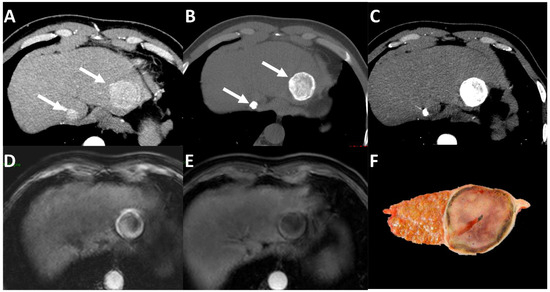

- Bae, J.S.; Lee, J.M.; Jeon, S.K.; Yoo, J.; Park, S.-J.; Yoon, J.H.; Joo, I.; Lee, K.-B.; Kim, H. LI-RADS Tumor in Vein at CT and Hepatobiliary MRI. Radiology 2022, 302, 107–115. [Google Scholar] [CrossRef] [PubMed]

- Lee, S.; Kim, S.H.; Lee, J.E.; Sinn, D.H.; Park, C.K. Preoperative gadoxetic acid–enhanced MRI for predicting microvascular invasion in patients with single hepatocellular carcinoma. J. Hepatol. 2017, 67, 526–534. [Google Scholar] [CrossRef]

- Renzulli, M.; Brocchi, S.; Cucchetti, A.; Mazzotti, F.; Mosconi, C.; Sportoletti, C.; Brandi, G.; Pinna, A.D.; Golfieri, R. Can Current Preoperative Imaging Be Used to Detect Microvascular Invasion of Hepatocellular Carcinoma? Radiology 2016, 279, 432–442. [Google Scholar] [CrossRef]